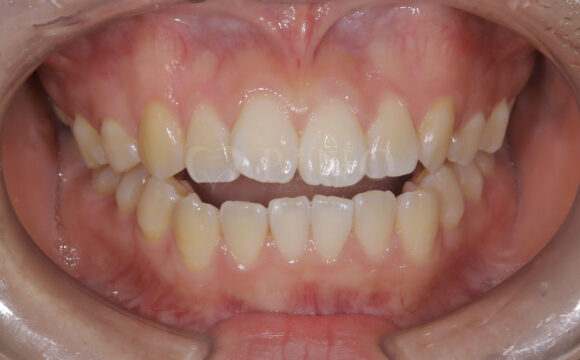

症例5:前歯が噛み合わないのが気になる(20代女性)

主訴 前歯が噛み合わないのが気になる 診断名 開咬 治療方法 マウスピース全顎矯正 抜歯 なし オルソパルス なし 治療期間 1年2ヶ月 費用 749,000円 副作用・注意点 非抜歯での治療のため、歯と歯の間をわずかに削る必要がある、矯正後の後戻りを防ぐためリテーナーの使用が必要となる 備考 奥歯に噛み合わせ不良がない場合、部分矯正が適応となる -